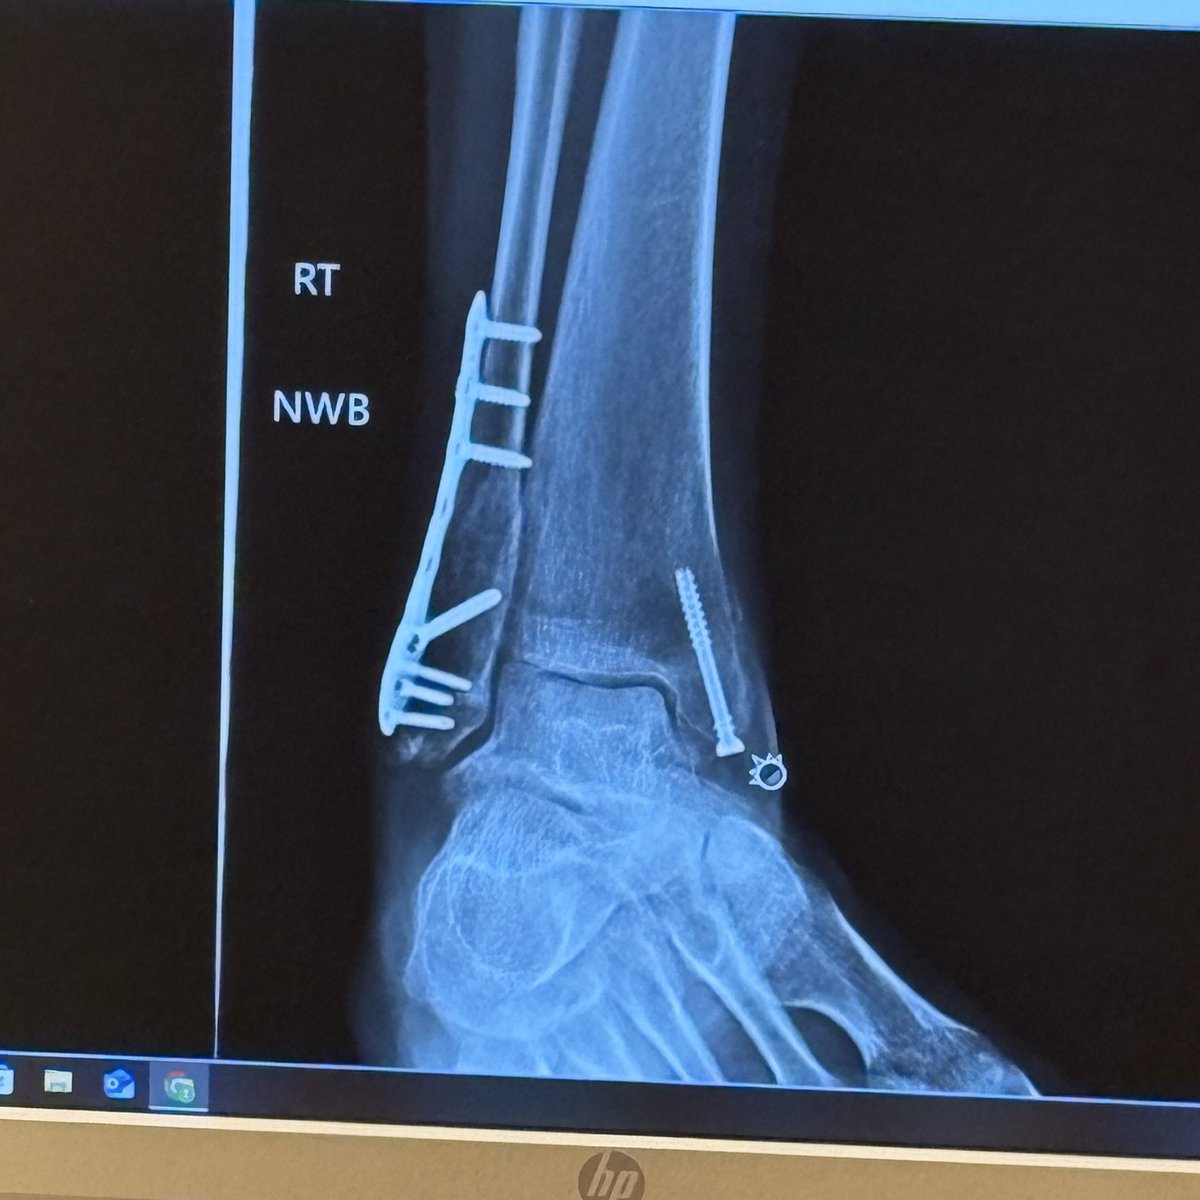

Got my cast off today felt sooooo good to have my leg/foot scrubbed finally 😅 Doc said everything healed perfectly, in 3 weeks I’ll be fully recovered...